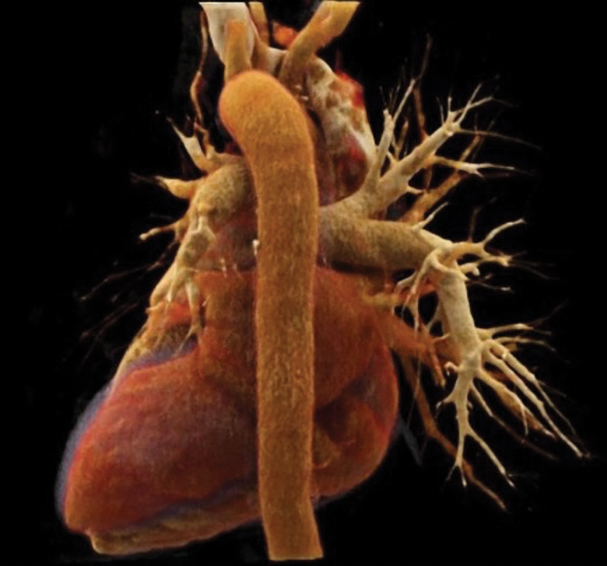

Figure 3

Cinematic VRT posterior view of the mediastinum; neither upper nor lower left pulmonary veins (in red color) are patent.